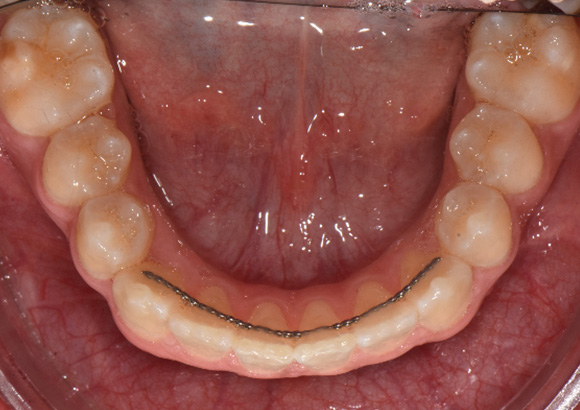

Le plan de rétention comprenait un appareil de rétention fixe sup. 2-2 et inf. 3-3 et des appareils de rétention Essix sup. / inf. Nous avons recommandé l’extraction de la dent de sagesse.

La position et l’angulation des incisives maxillaires ont été maintenues grâce au développement important de l’arcade postérieure et à l’excellent contrôle du torque antérieur. Dans l’ensemble, le patient s’est montré extrêmement coopérant avec l’utilisation des élastiques du début à la fin du traitement, mais il y a eu de nombreux problèmes en termes d’hygiène buccale. De point de vue efficacité clinique, le patient a eu 11 visites de traitement et a été soigné en 12 mois.